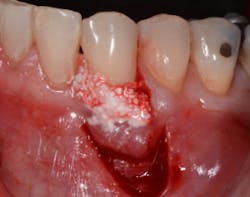

A horizontal mattress suture is then placed in the mucosa, which creates the vertical slope of the Y and advances the marginal part of the flap coronally above the recession defect (figures 4, 4a, and 4b). This tension-free coronal movement of the tissue is obtained by a zipper-like effect of the horizontal mattress (see the video at the end of this article).

Figure 4b